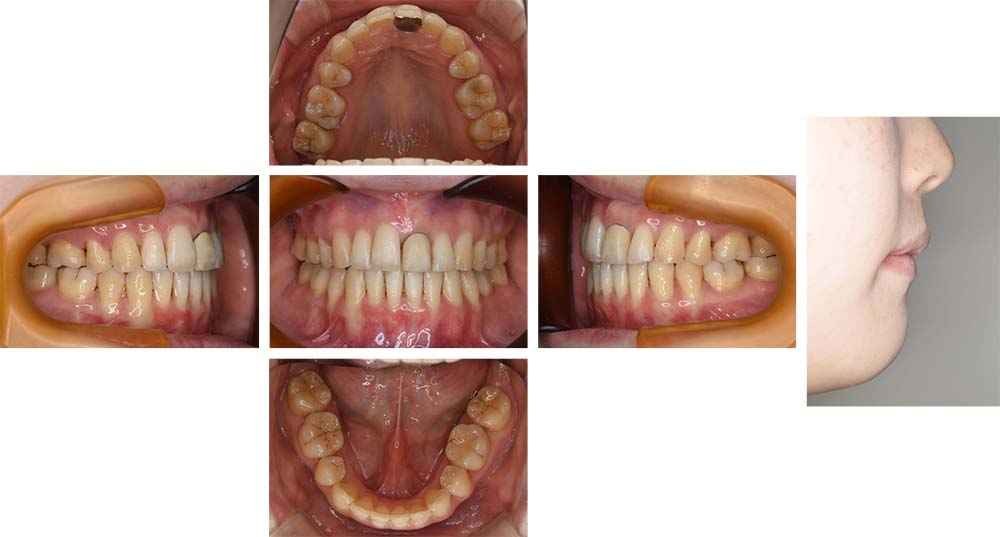

治療前

治療後

前歯が少し重なっている前歯部叢生を主訴として来院された。初診時ご相談時には口元に対しての要求はなかったが、口元の突出(俗にいうゴボ口)とガミースマイルについての説明をしたところ、治療対象とすることを希望された。分析の結果、上下顎前突と診断した。上下顎小臼歯抜歯を行っていただき、矯正用アンカースクリューを併用し上下顎舌側マルチブラケット装置を使用して動的治療を行った。叢生の改善と上下顎前歯の後退が十分に行われた。下口唇はE-ラインから+1㎜程度であったが、上口唇はE-ライン上まで後退させることができた。また、前歯の後退方向にも工夫を加えたことから、ガミースマイルもある程度改善した。動的治療期間2年1か月間。